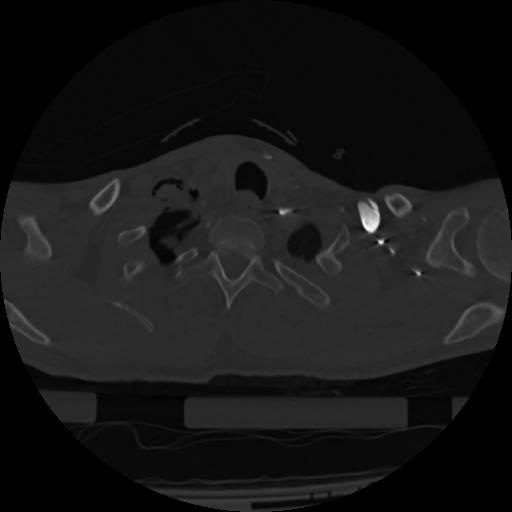

22 ANGIO,CE,Vol,0.5,ANGIO,,